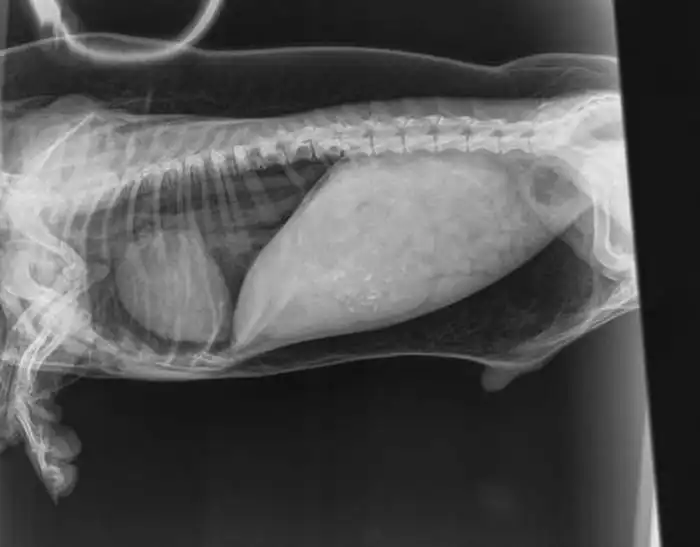

Также сделали рентген и выяснили, что внутри нее много воздуха. Оказалось, что в ее трахее образовалось микроскопическое отверстие, через которое воздух при каждом вдохе попадал внутрь собаки. Это явление называют подкожной эмфиземой, однако чем оно вызвано, неизвестно.